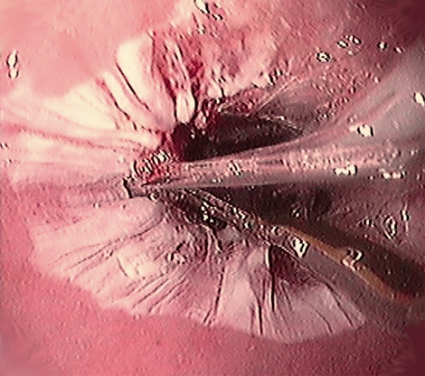

På senare år har det skett en kraftig incidensökning av adenokarcinom i esofagus i Sverige och västvärlden [1, 2]. Någon säker orsak till detta har inte kunnat påvisas, men sambandet med gastroesofageal refluxsjukdom är tydligt [3]. Av speciellt intresse är förekomsten av körtelmetaplasi, som ses hos cirka 5–10 procent av patienterna med gastroesofageal refluxsjukdom. Dessa förändringar har ett karakteristiskt endoskopiskt utseende, vilket gör att diagnosen ställs först vid endoskopiundersökningen. Körtelmetaplasi innebär att en del av det normalt förekommande skivepitelet i distala esofagus ombildats till körtelslemhinna. Om körtelslemhinnan innehåller bägarceller klassas den som intestinal metaplasi, vilket krävs för att den ska få kallas Barretts esofagus (Figur 1, Fakta 1). Dessa epiteliala körtelstrukturer kan därefter successivt utveckla olika grader av dysplasi (låggradig eller höggradig) och även progrediera till cancer (adenokarcinom).